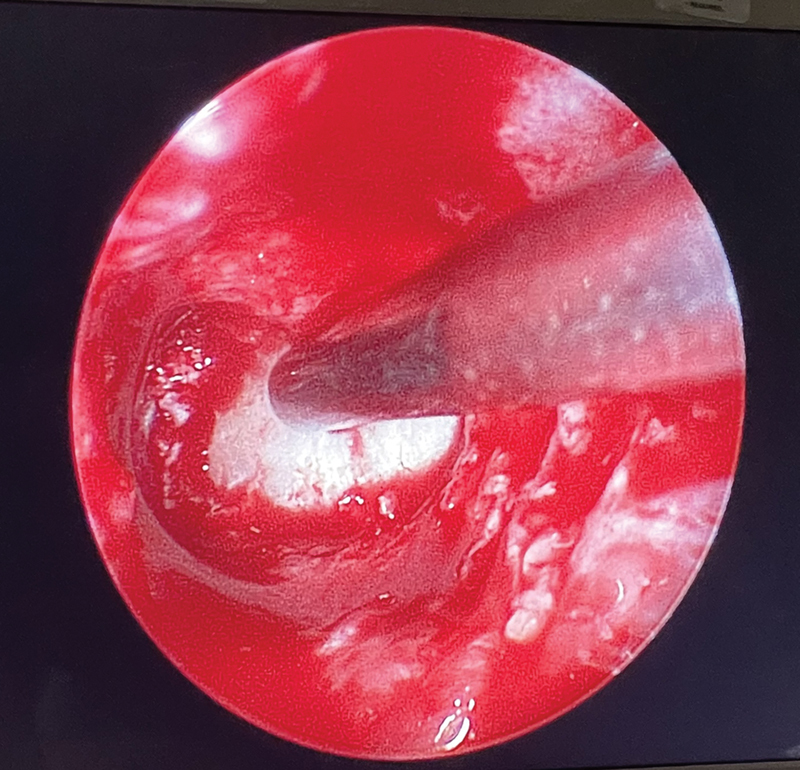

Case description: A 7-month-old male with a family history of osteopetrosis presented with hepatosplenomegaly. The infant was diagnosed with osteopetrosis based on radiological findings and genetic testing. Ophthalmologic examination and magnetic resonance imaging showed evidence of bilateral optic nerve compression. Endoscopic transcaruncular optic nerve decompression was not attainable The patient underwent a bilateral expanded endoscopic endonasal medial orbital wall and optic canal decompression.

Conclusion: This is one of the few reported cases of endoscopic endonasal optic nerve decompression surgery on an infant. Endoscopic endonasal optic nerve decompression surgery is a viable and effective treatment option for optic nerve compression in infants with osteopetrosis, especially in cases where cost of surgery is a limiting factor for patients. This approach provides direct access to the optic canal with minimal morbidity, offering significant potential for visual recovery, and an improved quality of life. Our patient represents the youngest reported infant in the literature, demonstrating the potential for undergoing this surgical approach at the earliest possible age to aid with his prognosis.